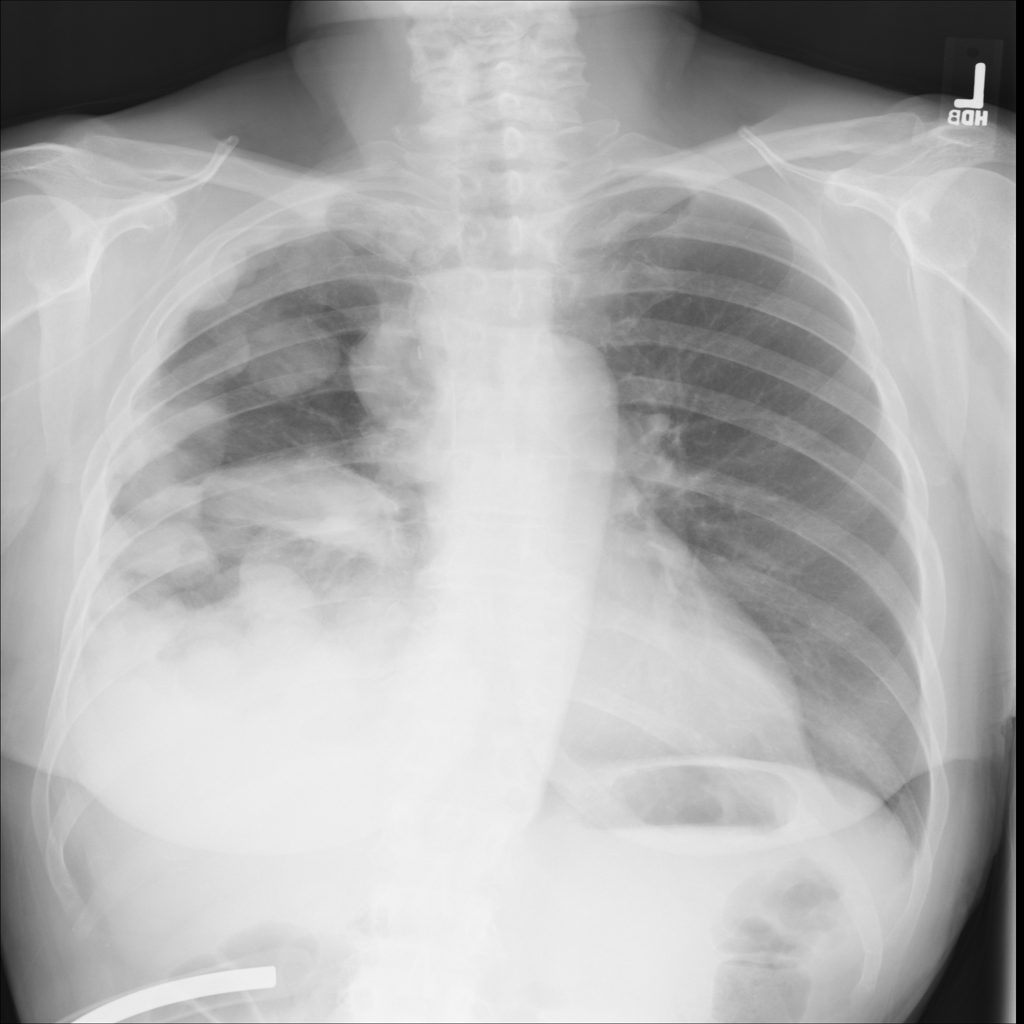

Mass

A mass is a larger focal opacity or lesion seen on the image. It is a descriptive finding that can have several causes and usually needs more imaging or clinical context to characterize.

PAT-50E5 · IMG-008Mass

PAT-50E5 · IMG-008

PA